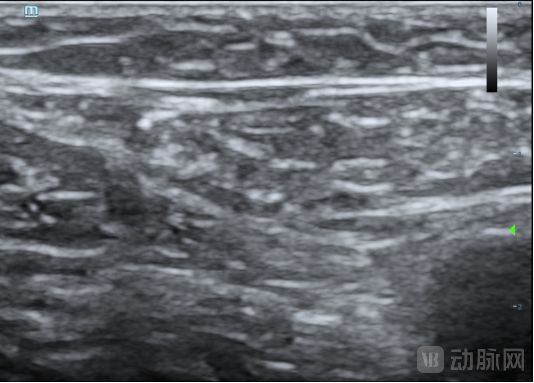

本次临床试验的入组患者为63岁男性,其静脉曲张符合本临床试验方案入选入排标准。经上海交通大学医学院附属第九人民医院陆信武主任团队对患者评估,选择使用恩盛医疗自主研发的VeSeal静脉闭合系统,在超声影像的引导下采用微创介入的方式将病变血管闭合,整个手术时间不到半小时。

据介绍,VeSeal静脉闭合系统不同于其他临床研究,VeSeal还配备了输送导丝及导管鞘管等标准配件,注射导管在超声下实时可见,鞘管具有标尺,手术过程无需其它配件,方便临床医生快速、便捷、高效的将病变血管闭合。